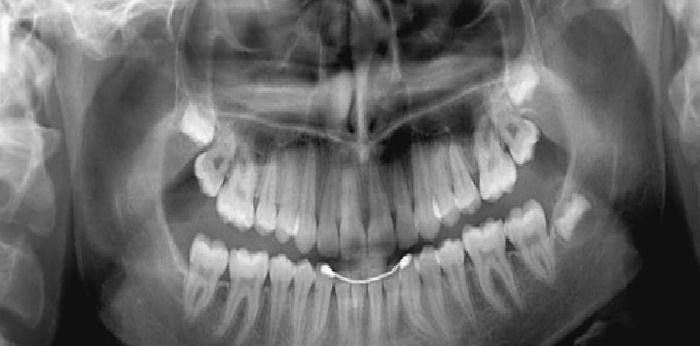

Panoramik röntgen, çenelerin, tüm dişlerin, çene ve dişlerdeki bir çok rahatsızlığın tek bir filmde

görülmesini sağlayan röntgen filmleridir.

Panoramik röntgen bir çok diş çürüğü, çenelerdeki kistik ve tümoral oluşumlarla ilgili erken teşhis olanağı

sağlar.

Tüm dişlerin görüntüsü tek bir röntgen üzerinde görülebilir.

Panoramik röntgen tüm dişlerin ve çene kemiğinin daha az ışın alarak birlikte görüntülendiği bir

tomografik röntgen çeşididir.